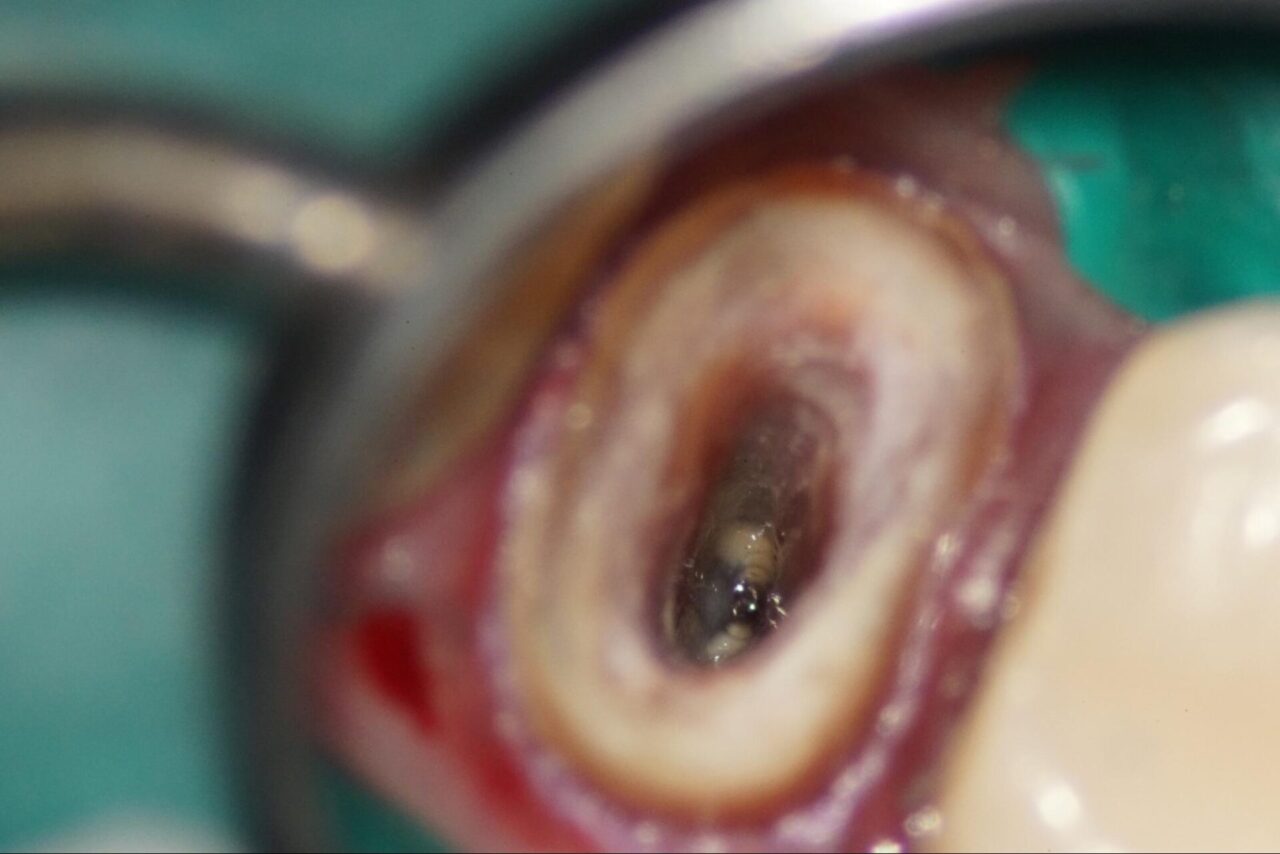

頬側根と口蓋根がつながっている事が確認できます。

以前の根管内の内容物を慎重に取り除いて行きます。

イスムと言われる根管内の複雑な形態が出て来ました。

以前の根管内にあるガッタパーチャを取り除いて行きます。頬側内壁にはクラックだと思われるスジ状のものが確認できます。

更に根尖部分を感染部除去を行っていくとこの様なものが出て来ました。液体は6%次亜塩素酸酸を有機質分解のために使用しています。